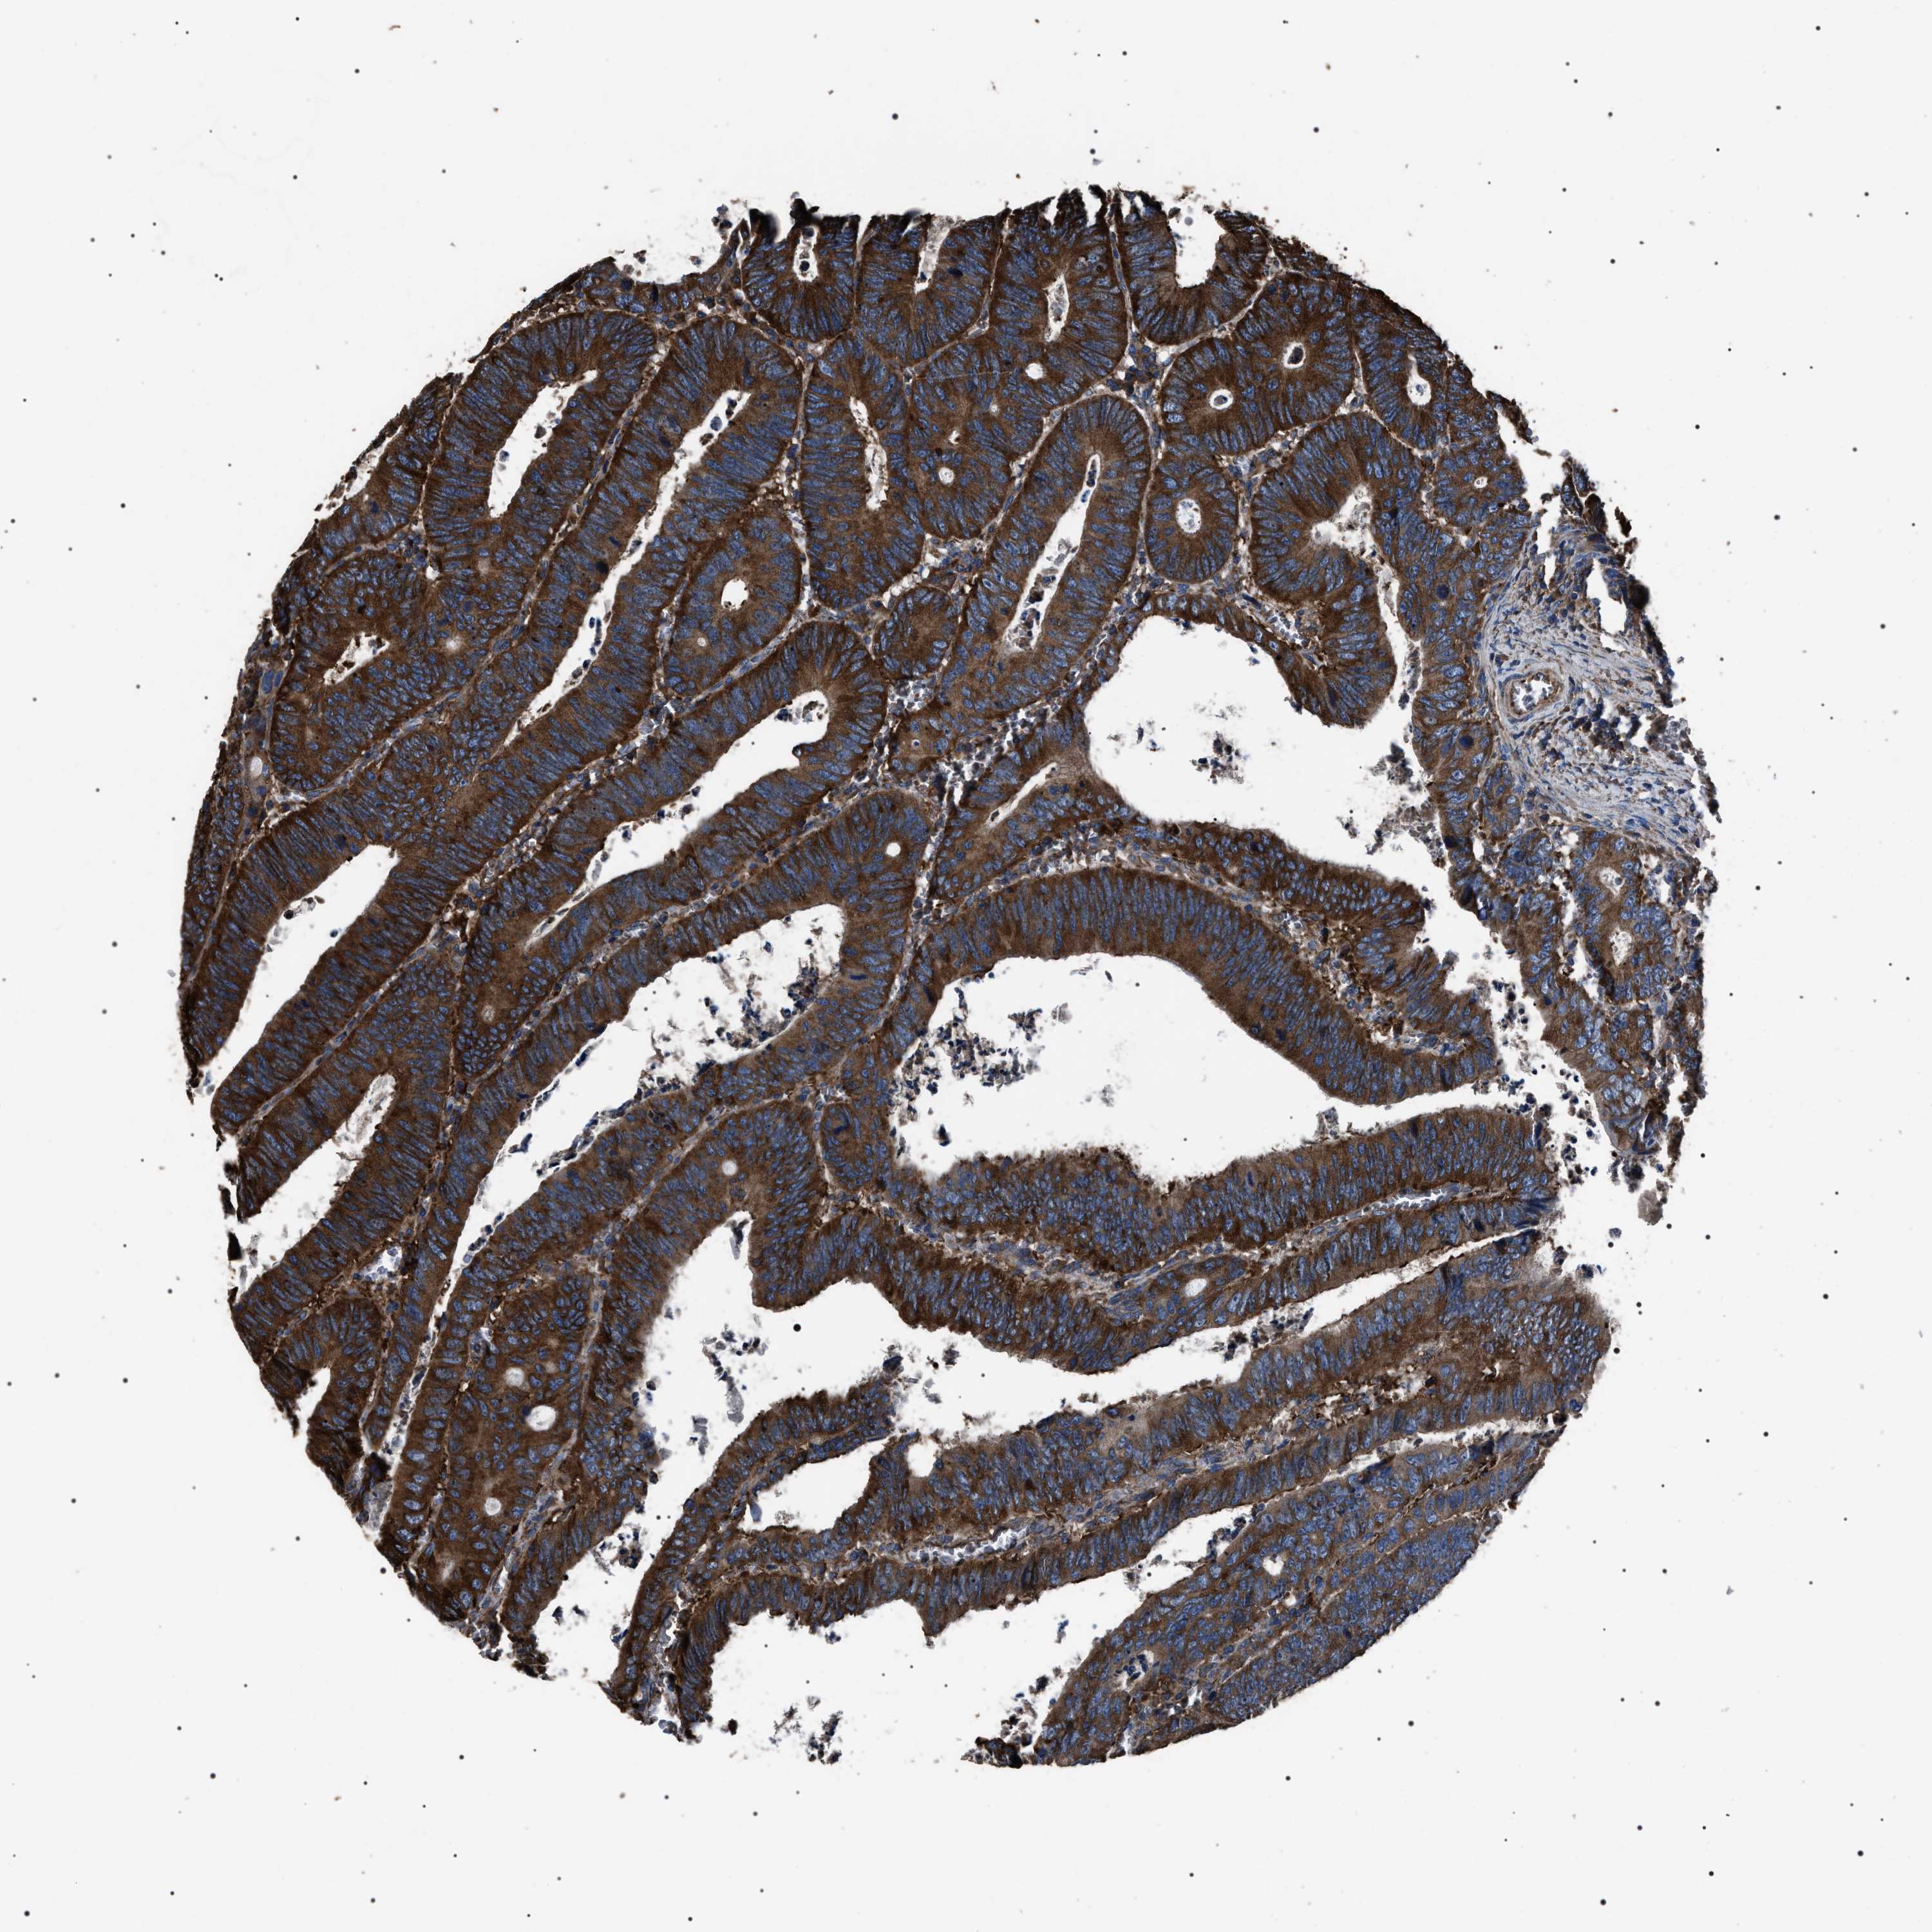

COLON ADENOCARCINOMA (VALIDATION) - Interactive survival scatter ploti

The Survival Scatter plot shows the clinical status (i.e. dead or alive) for all individuals in the patient cohort, based on the same data that underlies the corresponding Kaplan-Meier plots. Patients that are alive at last time for follow-up are shown in blue and patients who have died during the study are shown in red.

The x-axis shows the expression levels (FPKM) of the investigated gene in the tumor tissue at the time of diagnosis. The y-axis shows the follow-up time after diagnosis (years). Both axes are complimented with kernel density curves demonstrating the data density over the axes. The top density plot shows the expression levels (FPKM) distribution among dead (red) and alive patients (blue). The right density plot shows the data density of the survived years of dead patients with high and low expression levels respectively, stratified using the cutoff indicated by the vertical dashed line through the Survival Scatter plot. This cutoff is automatically defined based on the FPKM cutoff that minimizes the p-score. The cutoff can be changed by dragging the vertical line or by entering a cutoff value in the square labeled "Current cut-off".

Under the Survival Scatter plot the p-score landscape (black curve; left axis) is shown together with dead median separation (red curve; right axis). Dead median separation is the difference in median mRNA expression between patients who have died with high and low expression, respectively. It is calculated as follows: median FPKM expression of dead patients with high expression - median FPKM expression of dead patients with low expression. This is intended to aid the user in visually exploring custom cutoffs and the associated p-scores and dead median separation.

Individual patient data is displayed and can be filtered by clicking on one or more of the category buttons on the top of the page. Categories describing expression level and patient information include: high, low, alive, dead, female, male and tumor stages. The scale of the x-axis can be toggled between linear and log-scale by clicking on the "x log" button. Mouse-over function shows TCGA ID, patient information and mRNA expression (FPKM) for each patient.

& Survival analysisi

Kaplan-Meier plots summarize results from analysis of correlation between mRNA expression level and patient survival. Patients were divided based on level of expression into one of the two groups "low" (under cut off) or "high" (over cut off). X-axis shows time for survival (years) and y-axis shows the probability of survival, where 1.0 corresponds to 100 percent.

HSCB is not prognostic in Colon Adenocarcinoma (validation)

Best expression cut offi

Based on the FPKM value of each gene, patients were classified into two groups and association between prognosis (survival) and gene expression (FPKM) was examined. The best expression cut-off refers the FPKM value that yields maximal difference with regard to survival between the two groups at the lowest log-rank P-value. Best expression cut-off was selected based on survival analysis .

When clicking on this number, the vertical dashed line indicating cut-off, the interactive survival plot, and the Kaplan-Meier curve will be adjusted to show results based on the best expression cut-off.

: 5.19

Average pTPM 3.5

Number of samples 486